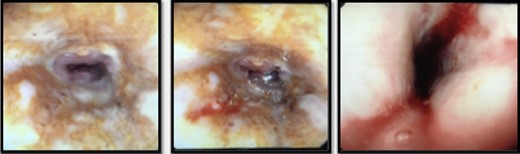

He was kept nil orally. Analgesia, antiemetics, IV proton pump inhibitor, and empirical IV antibiotics were commenced. Esophagastroscopy showed large hiatus hernia with reflux esophagitis. Middle-lower third esophagus appeared patchy, gangrenous from 27 cm to gastroesophageal-junction at 35 cm (Fig. 2). Multiple biopsies for viral culture and microbiology showed chronically inflamed cell infiltrates consistent with mucosal ischemia. No viral inclusions are seen. At the end of procedure, a PEG with jejunal extension tube was inserted to commence feeds.

Interval gastroscopy in 2 weeks showed healing mucosal ischemia with slough from 27–30 cm (Fig. 3). Clear fluids were commenced and gradually upgraded to normal diet. Follow-up CT showed no contrast extravasation within posterior mediastinum (Fig. 4) and gastroscopy in 8 weeks showed healed esophagus.

Healing mucosal ischemia from upper, mid and distal esophagus.